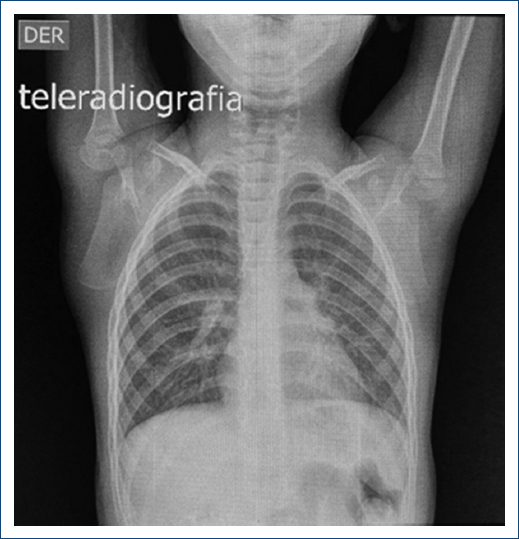

Complementary studies included a chest X-ray that revealed excavation of the lung button (Fig. 1) with no other relevant findings. The electrocardiogram showed ST depression, left ventricular growth with a positive Sokolow-Lyon index, suggesting signs of systolic overload and myocardial ischemia. The two-dimensional transthoracic echocardiogram confirmed concentric left ventricular hypertrophy; normal mobility; preserved ejection fraction of 70%; tri-leaflet aortic valve without alterations; the presence of severe SVAS with a maximum gradient of 116 mmHg and a mean gradient of 65 mmHg. The aortic annulus measured 10 mm (z-score-1.7); the sinuses of the Valsalva measured 14mm (z-score –1.3); and STJ measured 8 mm (z-score –3.6) (Fig. 2). These findings were confirmed with chest angiotomography (Fig. 3). Based on these findings, the diagnosis of SVAS was confirmed, and the decision was made to perform Doty’s procedure to resolve the stenosis. The girl is currently asymptomatic with regular cardiovascular follow-ups every 6 months.

Figure 1. Posteroanterior chest radiograph with a normal cardiothoracic index and button excavation pulmonar.